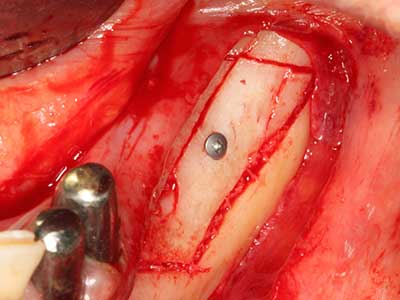

When surgical procedures are performed on bone in the immediate vicinity of sensitive structures such as blood vessels or nerves, rotary instruments pose a significant risk of iatrogenic injury. Piezoelectric devices can be helpful for preparation of bone covers and removal of hard tissue close to nerves, particularly for exposure of nerves after iatrogenic injury but also during nerve lateralization for resective and reconstructive procedures or implant placement (Fig. 17-20). Light contact between the piezotip and the nerve does not generally result in damage but proceeding incautiously with saw-like motions or attachments where a residual bone substrate remains may cause temporary or even permanent nerve damage. However, the risk of damage is considered to be substantially lower than when using saws or milling instruments (Pereira, Gealh et al. 2014).